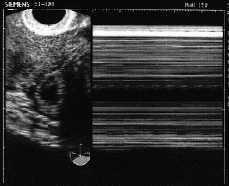

Figura 4. Imagen ecográfica de útero, con cavidad endometrial vacía y endometrio fino.

-- Útero de 76 * 36 * 52 mm con cavidad endometrial vacía y endometrio fino secretor.